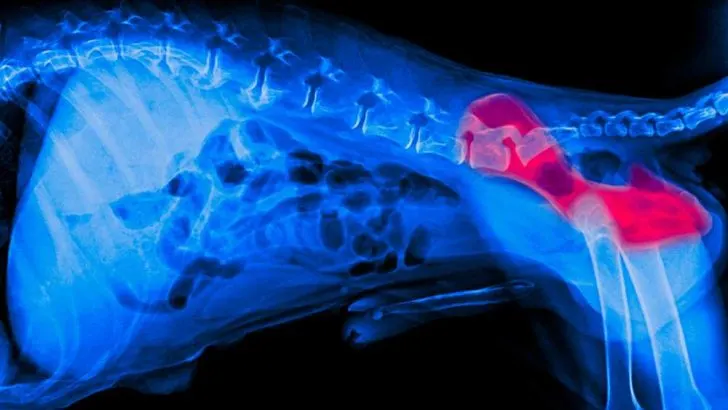

It’s essential to listen to your corgis at all times and help them out whenever you can. Take your corgi to your local veterinarian so that he can thoroughly examine what is wrong with your pup. In most cases, hip dysplasia is easily spotted with a simple x-ray scan.